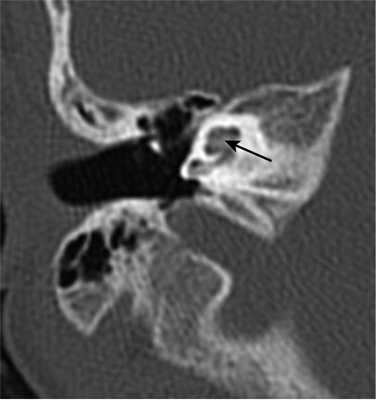

У одного пациента на КТ определялись двусторонняя аномалия внутреннего уха по типу Мондини (рис. 3), двусторонний локальный порок развития цепи слуховых косточек, костная облитерация лабиринта, включая улитку справа. На МРТ внутриулитковая жидкость справа не определялась, слева количество внутриулитковой жидкости было в норме.

Рис. 3. КТ, аксиальная проекция. Аномалия Мондини, состояние после КИ.